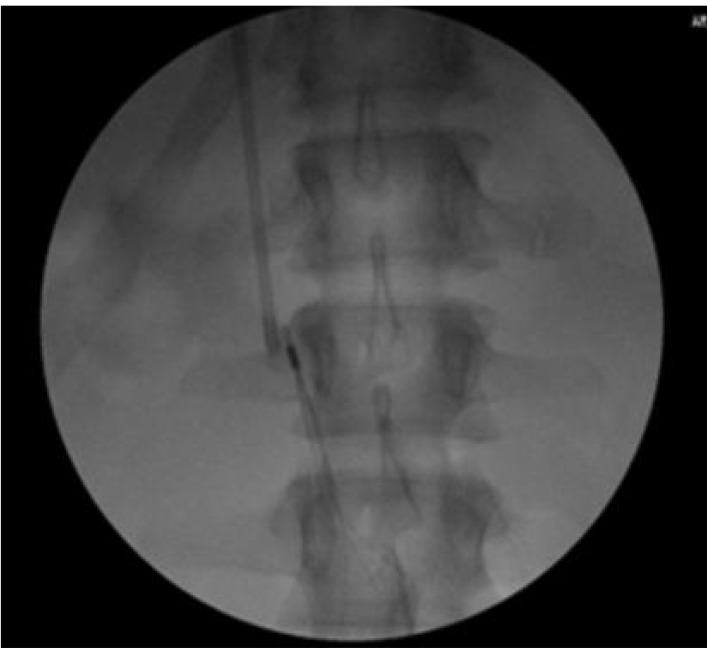

Case presentations: We had an equal number of males and females of the eight patients. Their ages ranged from 20 to 80 years. Five patients presented with bilateral lower limbs Deep vein thrombosis (DVT) of which one had a pulmonary embolism. Two other patients had extensive left femoral DVT and one had extensive IVC, iliac, femoral, and popliteal veins thrombosis. The medical records of seven patients, who had IVC filter placement in our department, were reviewed. The IVC filter was deployed with the aid of a C-arm fluoroscopic unit. In a single case, access was secured via an indwelling dialysis catheter.